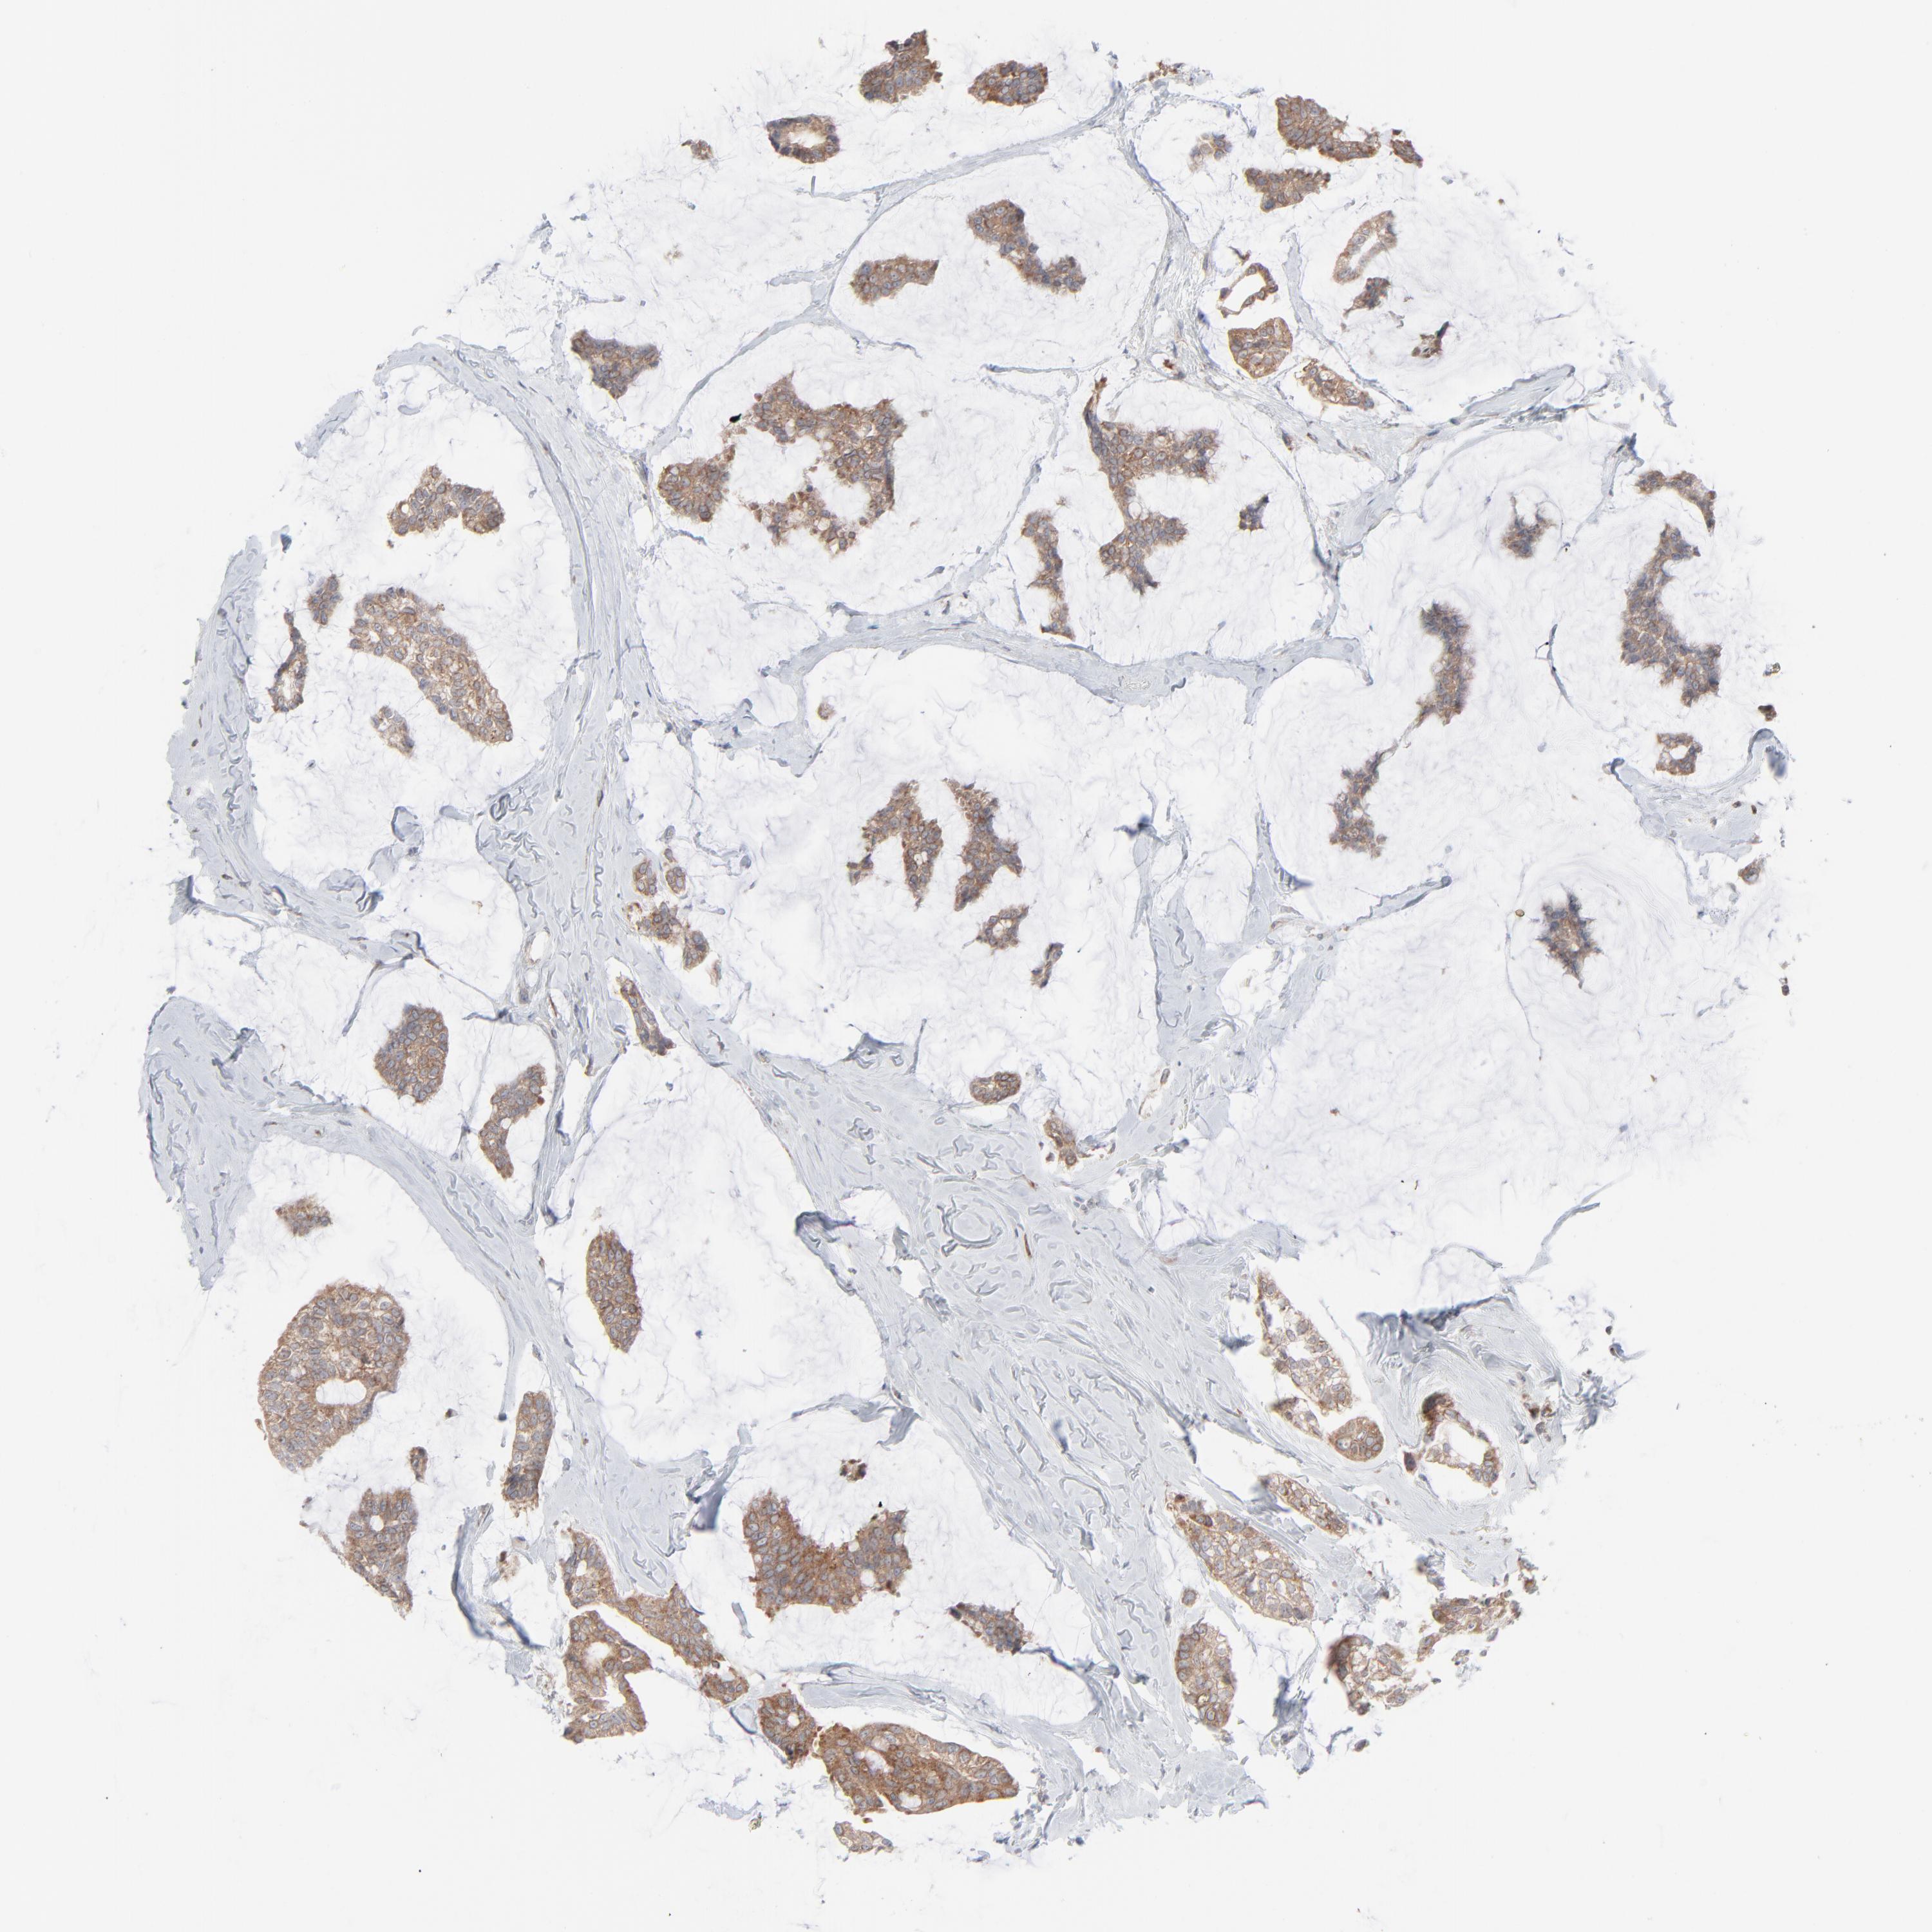

CANCER BREAST CANCER Show tissue menu

BRCA TCGA BRCA VALIDATION PROTEIN EXPRESSION

Breast cancer

Human cancer